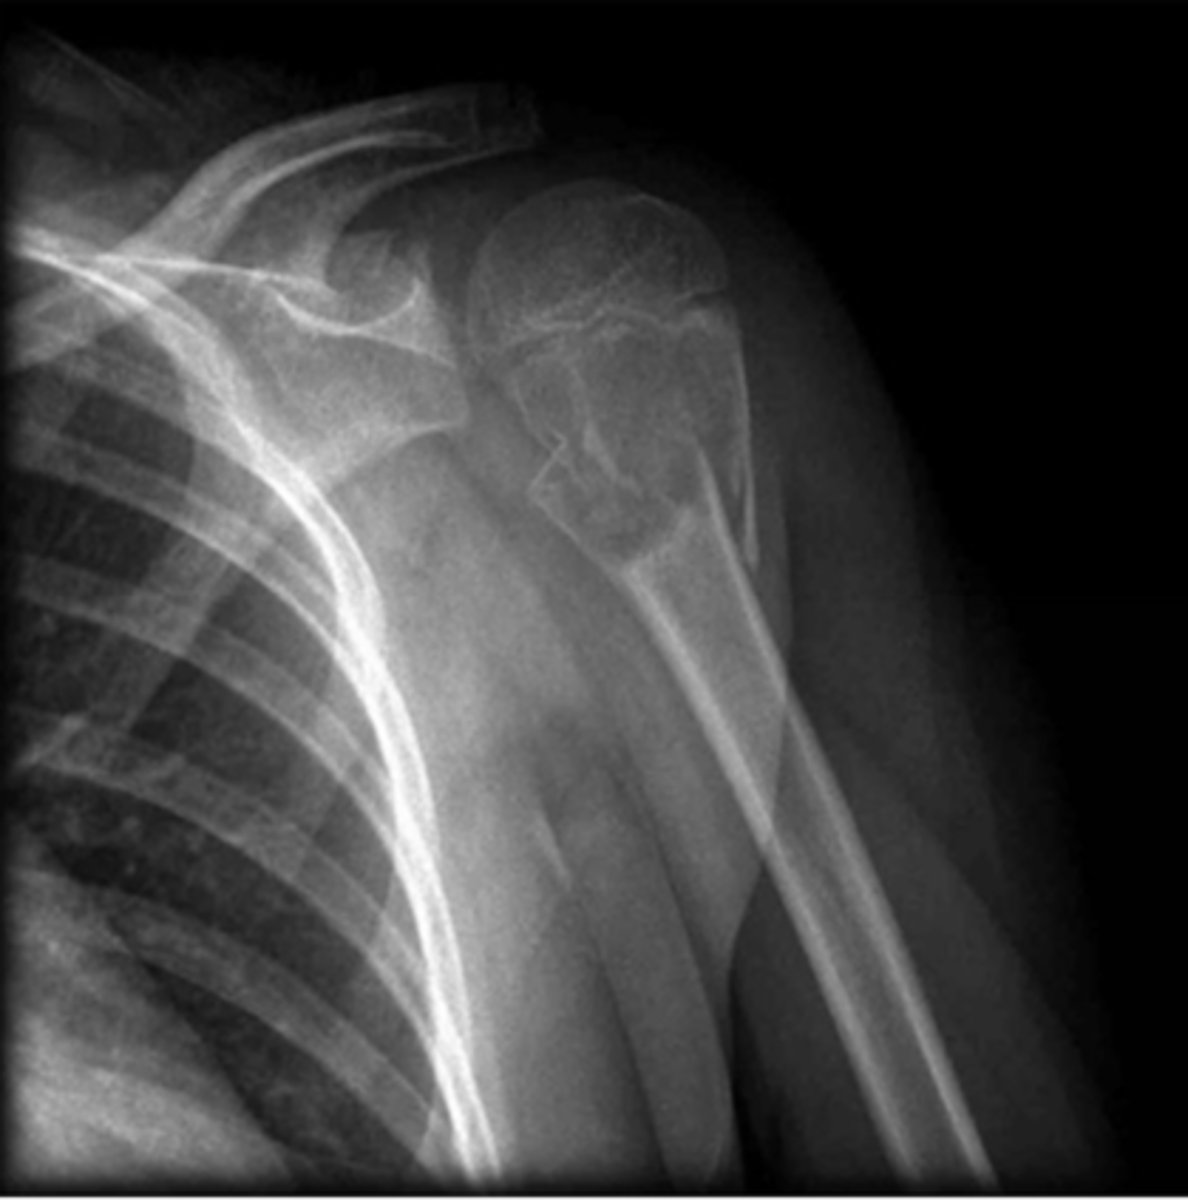

Fracture in which a portion of the bone (usually the fragmented end) protrudes though the skin

Compound fx